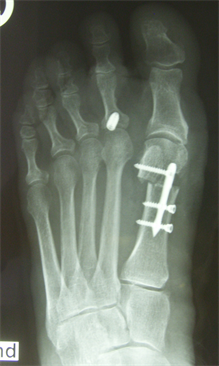

Figure 4. Patient Nr. 1: Recurrance of preoperated hallux valgus and hammertoe II.

Figure 5. Patient Nr. 1. Correction of a pathological DMAA without loss of length. Distal fragment has only a point contact to the proximal bone partner. Additional Akin osteotomy and PIP arthrodesis and FDL tranfer on the 2nd toe.

Figure 6. Patient Nr. 1. After 6 months the bone healing is completed with no loss of correction. Immediate full weigh bearing was allowed.